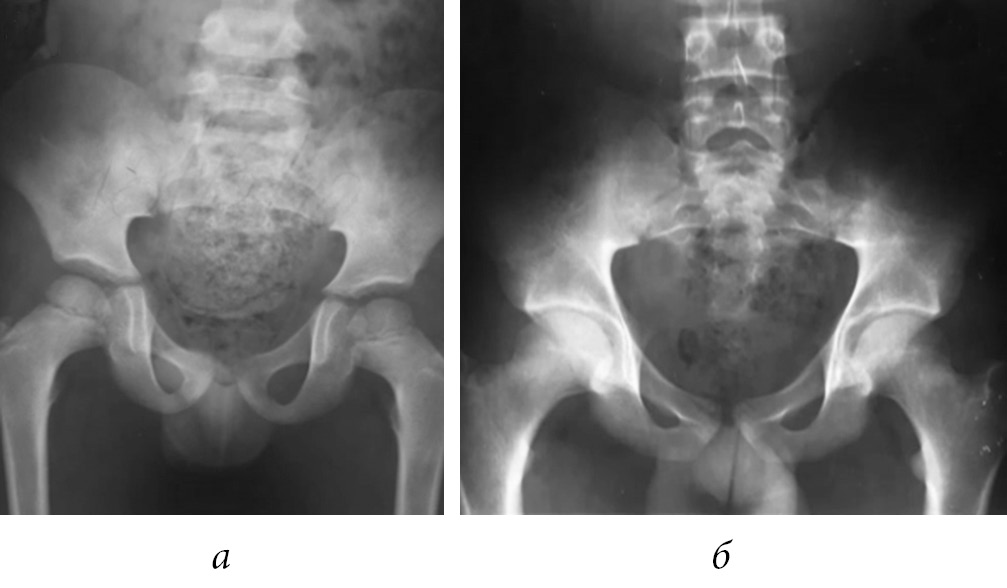

X-ray were obtained, they revealed incongruence of both coxofemoral joints, with posterior displacement of both femoral heads, without solutions of bone continuity (Fig. 1).

Fig. 1. Initial X-ray. Anteroposterior pelvis showing bilateral posterior hip dislocation (a); immediate postreduction X-ray. Pelvis with reestablishment of both coxofemoral joints (b)